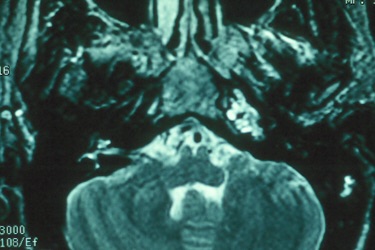

The petrous apex is a relatively inaccessible area that can occasionally harbor serious disease. Disease processes that usually cause symptoms are typically inflammatory or neoplastic in nature. Petrous apex lesions typically cause nonspecific symptoms such as headache, but as the lesion becomes more extensive, adjacent structures such as cranial nerves can become involved. A common early and specific sign of a petrous apex process is abducens palsy. Current imaging techniques can usually provide enough supplemental information to allow a focused plan of treatment. It is important to determine whether a petrous apex lesion can be observed or, if surgical treatment is required, whether a drainage or excision is required. There are various available surgical approaches to the petrous apex. The choice depends on the status of hearing function as well as the suspected pathology, which will dictate whether a drainage or excisional procedure is required.